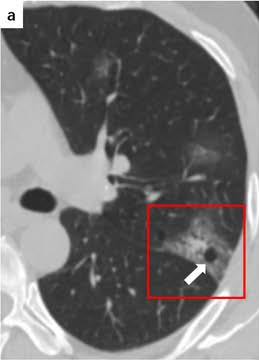

COVID19-CT dataset [51]: The dataset consists of a total of 746 CT images. There are 349 CT images of patients with COVID-19 and 397 CT images showing Non-COVID-19, but other pulmonary diseases. The positive CT images were collected from preprints about COVID-19 on medRxiv and bioRxiv, and they feature various manifestations of COVID-19. Since the CT images were taken from different sources, they have varying sizes between and . Figure 8 shows example CT images from the COVID19-CT dataset.

On the COVID19-CT dataset, the overall performance with respect to all evaluation metrics is inferior to that on the SARS-CoV-2 dataset. This can be attributed to the cross-source heterogeneity of the CT images in the dataset. The Non-COVID-19 CT images were taken from different sources and show diverse findings which pose difficulty to distinguish between COVID-19 and other findings associated with lung diseases due to the potential overlap of visual manifestations (see Figure 8). Another reason is that, the CT images in the COVID19-CT dataset show strong variations in contrast, variable spatial resolution and other visual characteristics, which could affect the model’s ability to extract more discriminative and generalizable features.

In a similar way, we consider classifying the test CT scans from the COVID-19 dataset by the DenseNet169 model and highlight the important regions considered for predictions. We present the original CT images and their localization maps in Figure 13. We can also see that our model is capable to detect the COVID-19 related regions as marked (small square in some images) by expert radiologists.

A wide variety of typical and atypical CT abnormalities have been reported for COVID-19 patients in various studies [58, 59]. So, we tested our models on external CT images extracted from these two publications as they feature typical findings of COVID-19 pneumonia marked by specialists. In order to make sure that not any of the extracted images are unintentionally included in our datasets, specifically the COVID19-CT dataset, we use the model trained on the SARS-CoV-2 dataset. First, the InceptionV3 model is employed to classify the extracted CT images. The model is able to correctly classify the given CT images as COVID-19. Second, in order to interpret the model’s generalization capabilities, we apply the Grad-CAM technique to visualize the regions of abnormalities that are considered. By assessing the different CT images in Figure 15, we can see that the model accurately localizes the disease-related regions. Even more interesting is the fact that the model ignores any specific marks in the images like letters and only localizes the COVID-19 related regions. These visual explanations show the success of our models to learn relevant, generic visual features related to COVID-19 and are capable to correctly classify CT images outside the datasets on which they are trained.

Figure 16 shows various CT scans where only one lung is visible. The CT scans are also extracted from the paper [58] and show different CT manifestations of COVID-19 pneumonia marked by red squares. The InceptionV3 model is capable to classify them correctly as COVID-19, although it is trained on CT scans where the entire lung is visible. Intriguingly, when applying Grad-CAM we can see that all regions of abnormalities are accurately localized. This also proves the potential of our model to detect COVID-19 abnormalities in CT images outside the dataset used for training.